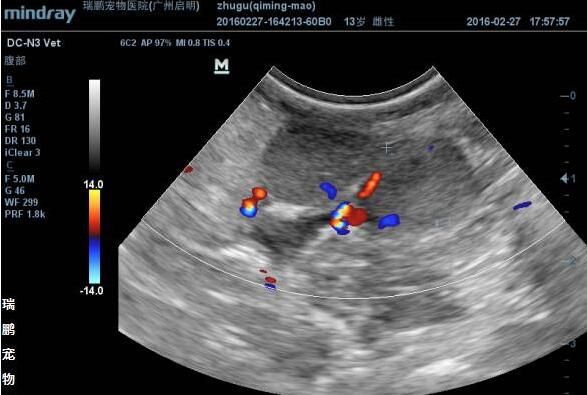

3.5 B超检查:左侧倒数第二个乳头肿块皮下可见一边界不清晰、质地不均的中等回声、呈蜂窝状团块,团块中央可见直径约0.53-0.88cm的无回声暗区(见图3);左侧倒数第三个乳头肿块皮下可见一边界清晰,中等均质回声圆形结节,实质可见血流供应(见图4)。腹股沟淋巴结皮下可见数个边界清晰,低等均质回声圆形结节,结节直径约0.69-2.34cm,边缘及实质血流供应丰富(见图5)。

图3 左侧倒数第二个乳头B超图片

图4 左侧倒数第三个乳头B超图片

图5 腹股沟淋巴结B超图片